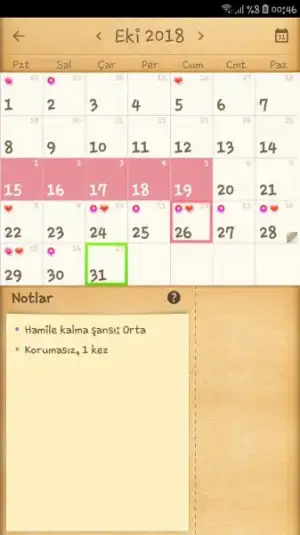

Bende yumurtlama öncesi değerlendirdim bu ay hep senin yine yakın benim takvimi görsen bu kendini nasıl gebe sanıyor der ağlarsın. Milletin kocasının spermler taş gibi taş 4 gün önceden gebe bırakıyor nerdeee bende o şans

Aferin kız :) senin şansın çok iyi bak. Ben çalışmalayı en son yumurtlamadan 2 gün önce yaptım